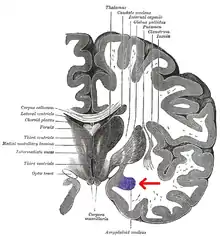

The regions described as amygdala nuclei encompass several structures of the cerebrum with distinct connectional and functional characteristics in humans and other animals.[5] Among these nuclei are the basolateral complex, the cortical nucleus, the medial nucleus, the central nucleus, and the intercalated cell clusters. The basolateral complex can be further subdivided into the lateral, the basal, and the accessory basal nuclei.[3][6][7]

Frontal and side view of amygdala

Amygdala along with other subcortical regions, in glass brain.

Dorsal view of the amygdalae in an average human brain

Frontal view of the amygdalae in an average human brain

Left lateral view of the amygdala in an average human brain